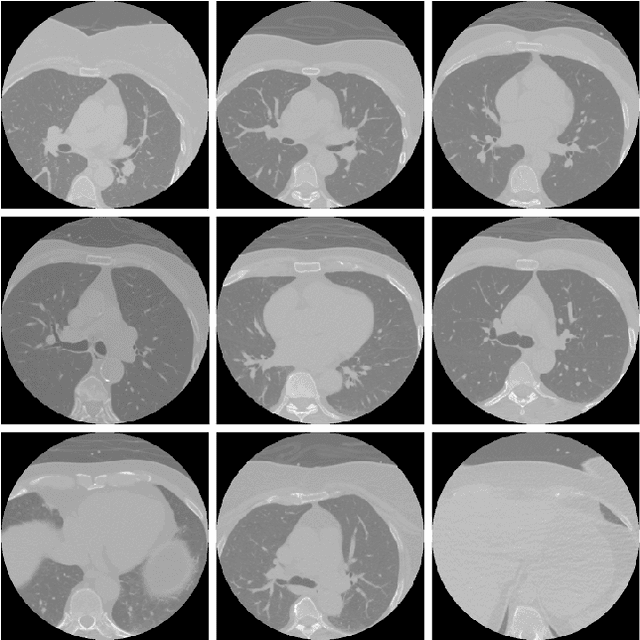

Abstract:Coronary artery diseases are among the leading causes of mortality worldwide. Timely and accurate diagnosis, facilitated by precise coronary artery segmentation, is pivotal in changing patient outcomes. In the realm of biomedical imaging, convolutional neural networks, especially the U-Net architecture, have revolutionised segmentation processes. However, one of the primary challenges remains the lack of benchmarking datasets specific to coronary arteries. However through the use of the recently published public dataset ASOCA, the potential of deep learning for accurate coronary segmentation can be improved. This paper delves deep into examining the performance of 25 distinct encoder-decoder combinations. Through analysis of the 40 cases provided to ASOCA participants, it is revealed that the EfficientNet-LinkNet combination, serving as encoder and decoder, stands out. It achieves a Dice coefficient of 0.882 and a 95th percentile Hausdorff distance of 4.753. These findings not only underscore the superiority of our model in comparison to those presented at the MICCAI 2020 challenge but also set the stage for future advancements in coronary artery segmentation, opening doors to enhanced diagnostic and treatment strategies.